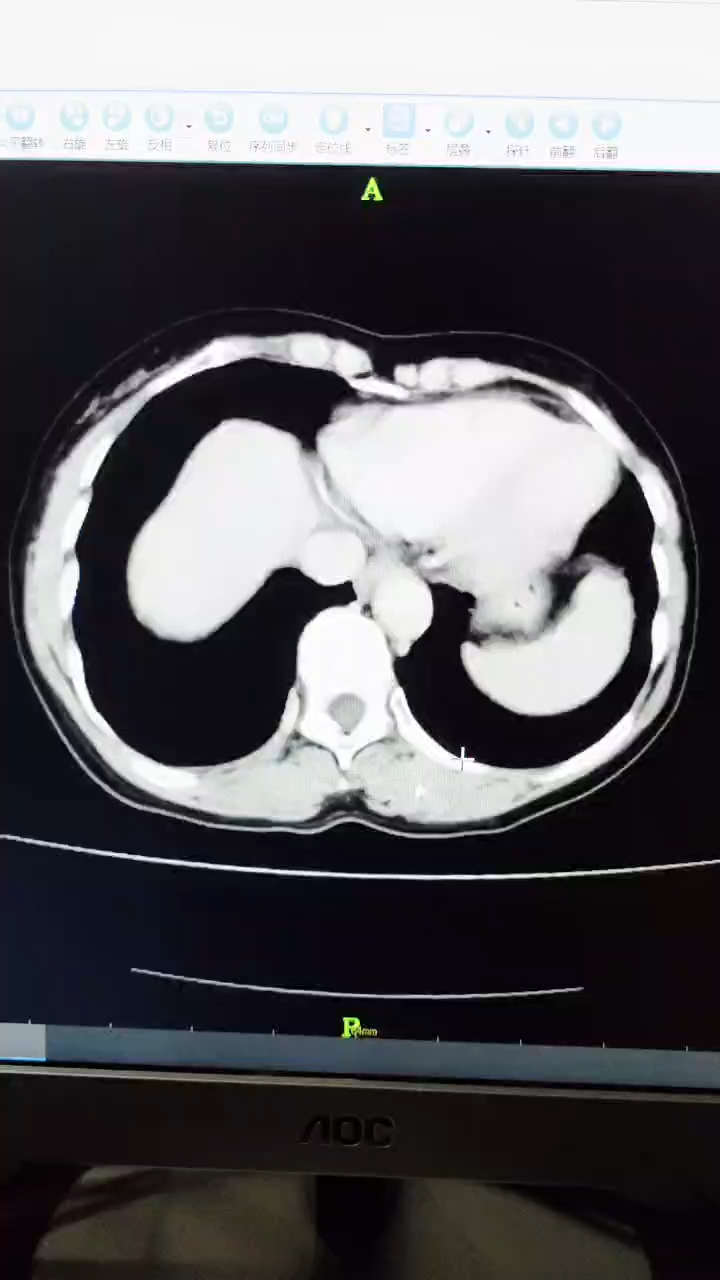

辅助检查:腹部B超提示上腹部不规则低回声包块,腹部CT检查提示腹腔多发占位性病变,考虑良性可能(如下图所示)。

动脉期

门脉期

延迟期

临床诊断:腹腔多发占位性病变性质待查。